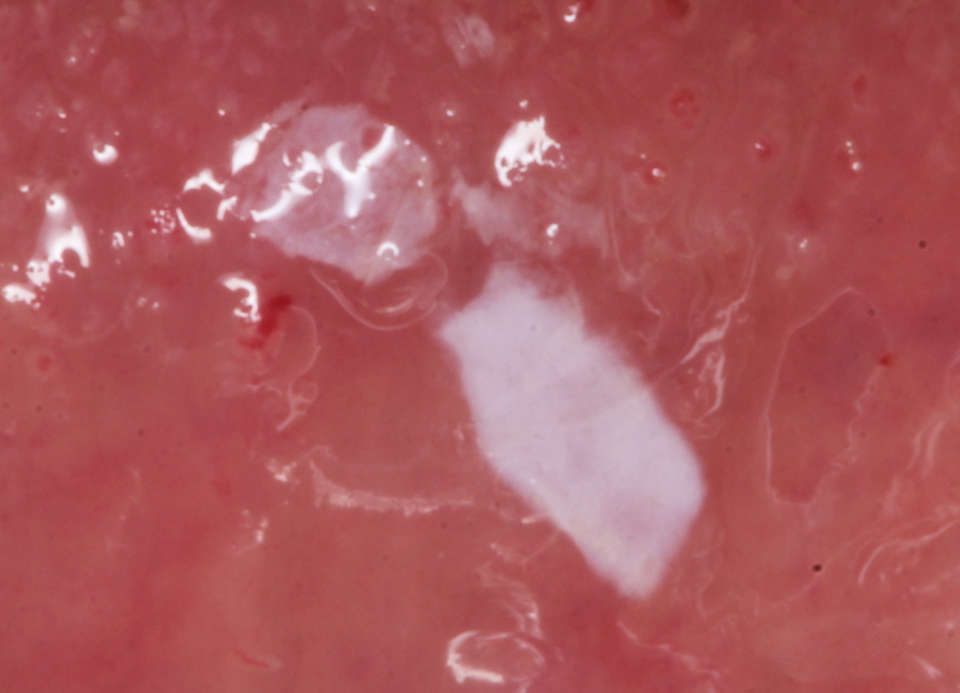

残根上のCR(ダイレクトボンディング)8 2025.11.12

ブリッジ脱離で2次カリエス+Perでグラグ… 2025.11.01